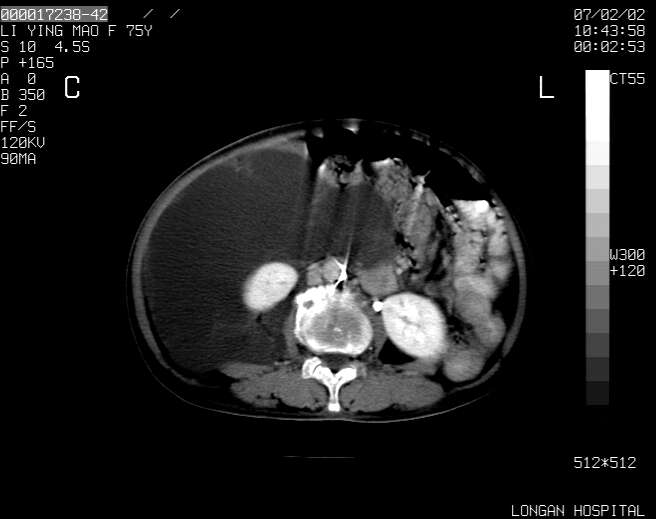

以下是引用dyqct在2007-2-10 8:53:00的发言:[br]考虑:1、肝脏多发囊肿[br] 2、左肾囊肿,右肾多发结石并积水。[br] 3、右胸少量积液。[br] 4、右肾周包裹性积液或淋巴管瘤(有见缝就钻的征象、薄隔、小结节状钙化)?[br] 5、腰椎动脉瘤样骨囊肿?[br] [br] [br]